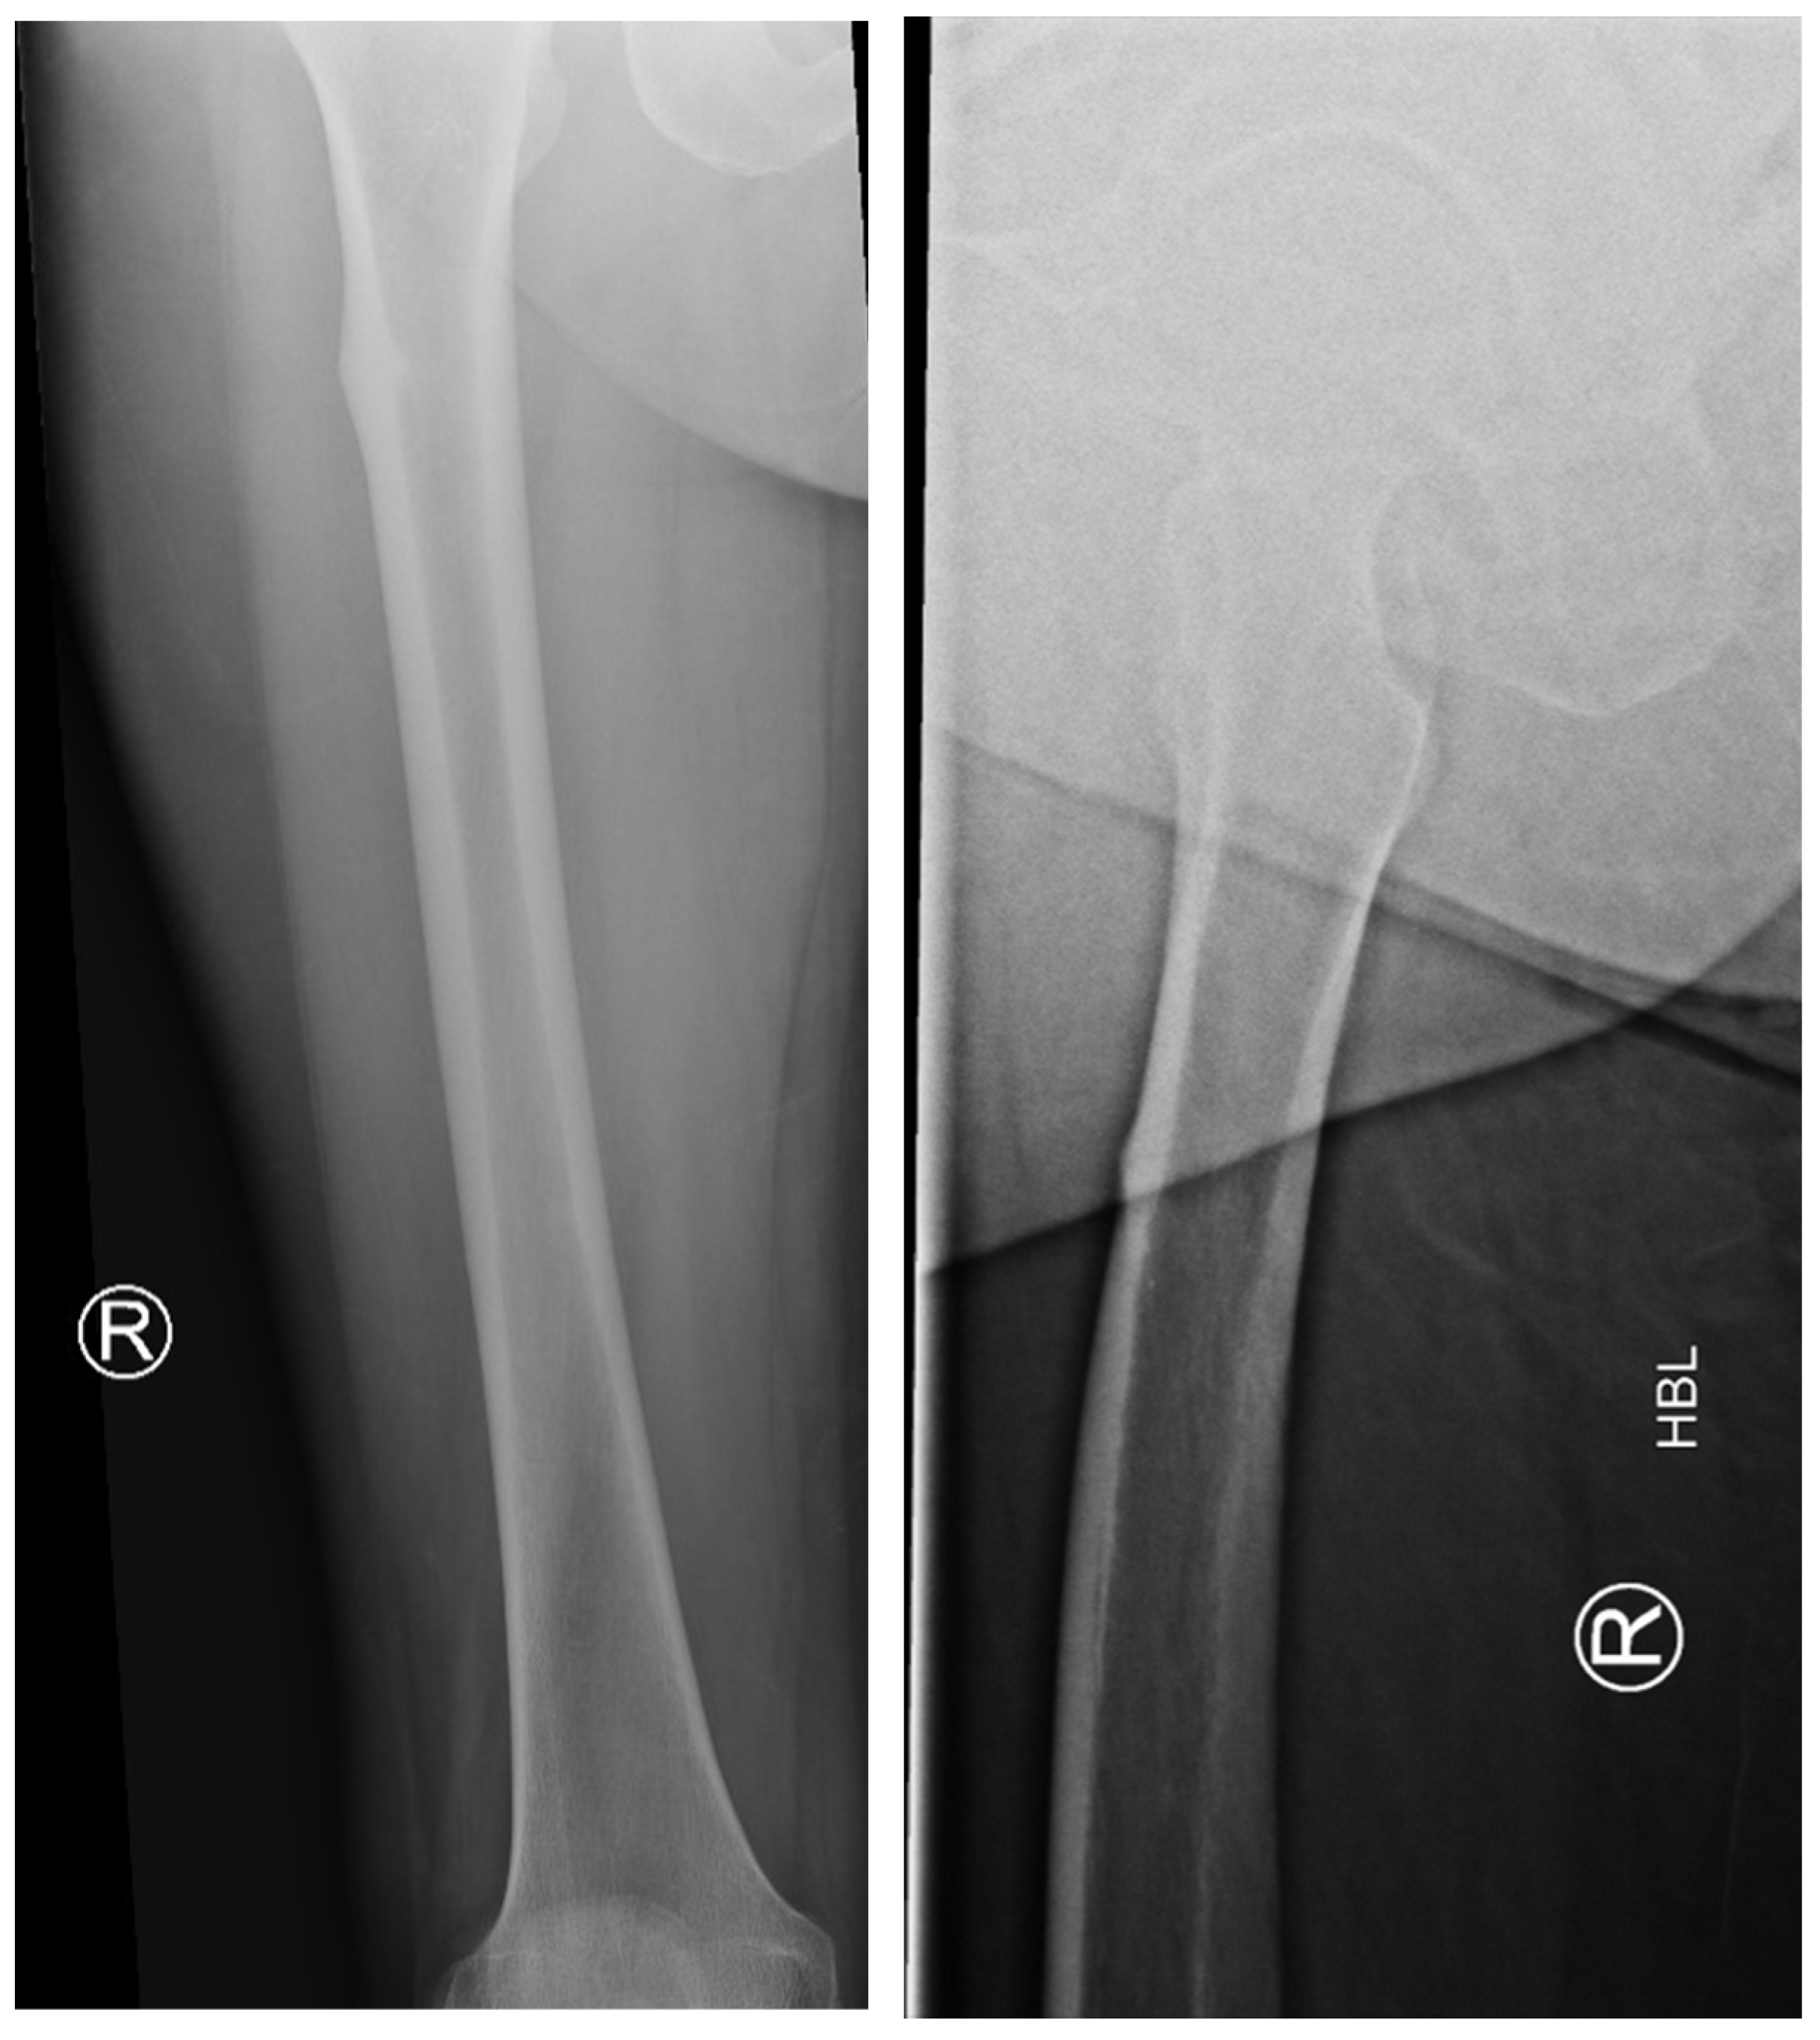

The following radiographs present the initial radiographs from the day of injury along with those obtained during the final OPD follow-up of the patient. The sequence presents radiographs demonstrating full radiological union (Scheme 1 and Scheme 2) and X-rays with no evidence of fracture healing at the final OPD follow-up (Scheme 3 and Scheme 4).

Scheme 1. X-ray of right hip AP view (left) and lateral view of right proximal femur (right) of atypical subtrochanteric fracture—September 2023.

Jcm 14 02858 sch001

Scheme 2. X-ray of right femur AP view (left) and lateral view of right hip (right) of atypical subtrochanteric fracture—September 2024 (radiological union).

Jcm 14 02858 sch002